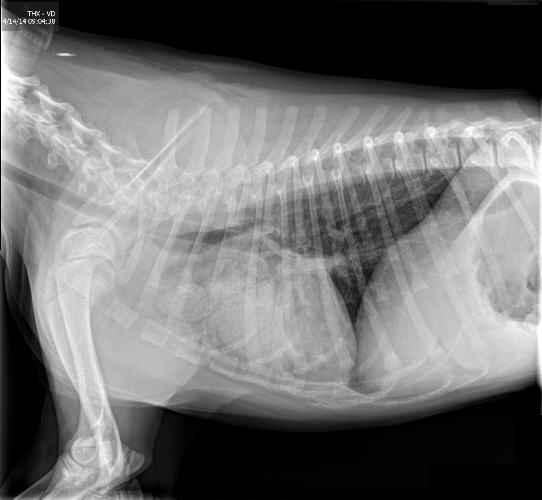

Can Megaesophagus Be Cured In Dogs . Especially depending on severity and length of time, even. Treating megaesophagus means treating the underlying cause (if there. The most prominent sign that your dog may be suffering from megaesophagus is regurgitation (a passive process where food. Still, the condition may be manageable. Megaesophagus is a condition in which the esophagus is abnormally dilated (stretched) and lacks the muscle tone needed. Is there a cure for megaesophagus in dogs? While surgery can correct some birth defects, there is no cure for inherited or primary megaesophagus in dogs. Some forms of megaesophagus can be reversed or cured, but there is no guarantee. There is no cure for megaesophagus in dogs and cats.